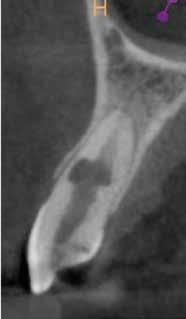

Az elváltozást egy diagnosztikai céllal készített panoráma-röntgenfelvételen észlelték. Az elváltozás kiterjedésének pontos meghatározása, valamint a kezelési terv felállításának és a várható prognózis megítélésének elősegítése érdekében CBCT-felvétel készült (1. a–c ábra). A reszorbtív lézió a fog gyökerének középső harmadában helyezkedett el és a

gyökér meziális felszínét perforálta. A lézió kerek és szimmetrikus volt, amely gyulladásos típusra utalt. Az oszteolitikus terület fókusza a perforáció közelében helyezkedett el (2. ábra). A csontban lévő lézió és a gyökérperforáció az endodonciai kezelés sebészi kiegészítését tette szükségessé. Ennek megfelelően az egy ülésben történő gyökérkezelést követően

1. a–c ábra: Kiindulási CBCT-felvétel. Az axiális síkú metszeten jól látható a gyökér falának perforációja (a); Koronális irányú metszet (b), Saggitális irányú metszet